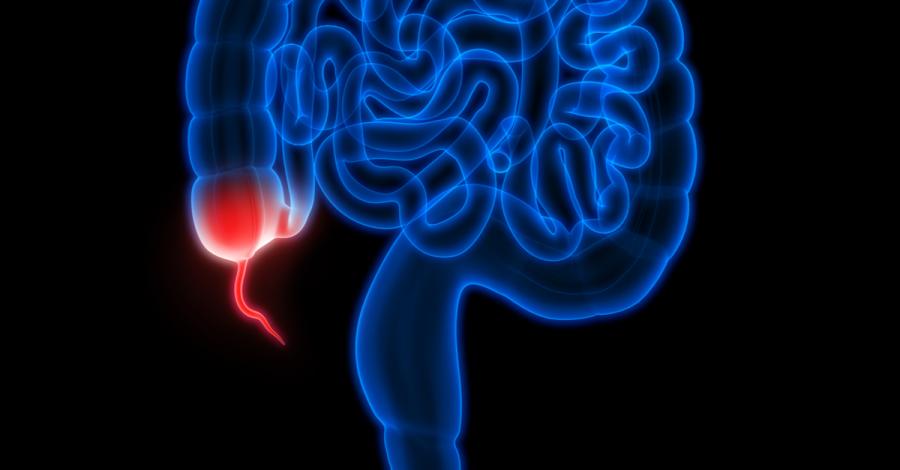

Анализ на приблизително 1,7 млн. души разкри любопитна връзка между апендикса и болестта на Паркинсон. Изследването показва, че хората, на които този орган е бил отстранен заради апендицит, са 25% по-малко предразположени към развиването на болест на Паркинсон (в зависимост от своето местоживеене).

Нещо повече - апендиксът (израстък на сляпото черво) е богат и на протеина алфа-синуклеин, който образува плаки в мозъците на болни от Паркинсон пациенти.

Невроучени от цял свят сравняват данните от инициативата Parkinson's Progression Markers с тези от Швецкия национален регистър на пациентите, за да открият връзка между неврогенеративното заболяване и апендектомията. Подобно начинание не е толкова странно, колкото изглежда на пръв поглед. Все повече проучвания показват, че Паркинсон води началото си от стомаха и си проправя път през блуждаещия нерв към мозъка (един от първите симптоми на болестта е запек).

Анормални количества от протеина алфа-синуклеин също са били забелязвани в гастроинтестиналния тракт. Той започва да се натрупва вследствие на имунна реакция към токсини и бактерия. Чревообразният апендикс пък често изпълнява ролята на "бомбово убежище" за чревната микрофлора. Ето защо учените решават да потърсят връзка с Паркинсон именно в тази област на човешкото тяло.

"Въпреки че апендиксът има репутацията на сравнително безполезен орган, той е ключов за нашата имунна система, като регулира натрупването на бактерии в червата, а сега, както показват и нашите данни, има пряка връзка с болестта на Паркинсон", коментира д-р Вивиън Лабри от изследователския институт "Ван Андел" в Мичигън.

Въпреки че апендектомията забавя появата на Паркинсон със средно 3,6 години, д-р Лабри смята, че не трябва да се прибързва с премахването на апендикса. "Би било много по-разумно да контролираме или да намаляваме прекомерното образуване на алфа-синуклеин", допълва тя.